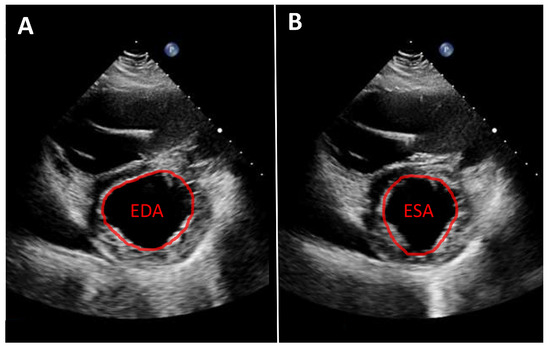

Routine Echocardiographic Assessment in LVAD Patients—A Structured Approach to Acquisition and Interpretation

by Nicolas Merke, Felix Schoenrath, Evgenij Potapov and Jan Knierim

J. Cardiovasc. Dev. Dis. 2026, 13(2), 70; https://doi.org/10.3390/jcdd13020070 - 30 Jan 2026

Durable left ventricular assist devices (LVADs) are an established and highly effective therapy for patients with advanced heart failure. Ongoing technological improvements and structured follow-up programs have significantly enhanced device durability, reduced complications, and improved long-term survival. Consequently, a growing number of patients with LVAD support require long-term outpatient care and increasingly present to both specialized and non-specialized hospitals, including for admissions unrelated to heart failure. In this context, echocardiography plays a central role. It is essential not only for routine follow-up at dedicated LVAD clinics but also for the assessment of cardiac status during inpatient admissions for extracardiac conditions. However, echocardiographic evaluation in LVAD patients is technically demanding and requires a solid understanding of LVAD physiology, device–heart interactions, and the specific hemodynamic conditions of continuous-flow support. Without this knowledge, standard echocardiographic parameters may be misleading. This review provides sonographers and cardiologists with a practical, clinically oriented framework for routine transthoracic echocardiography in patients with durable LVAD support. We summarize key principles of LVAD hemodynamics, discuss interpretation of LVAD console parameters, propose a standardized imaging protocol, and outline a structured approach to common echocardiographic findings in routine ambulatory and inpatient settings. Full article